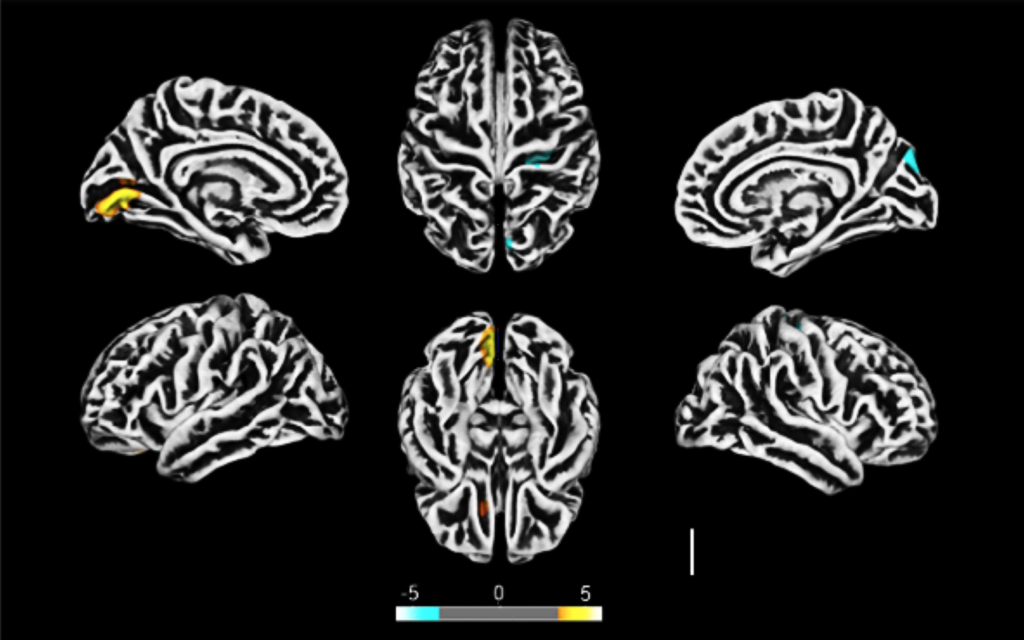

Para chegar a essa hipótese, o estudo realizou um percurso com diversas etapas e diferentes abordagens. O primeiro passo foi comparar imagens de ressonância magnética cerebral de 145 indivíduos saudáveis e de 81 pessoas com casos moderados de Covid-19, que não tiveram necessidade de suporte respiratório. O resultado mostrou que os participantes infectados muitas vezes manifestavam alterações na espessura cortical do cérebro, que estava reduzida no giro lingual esquerdo, no sulco calcarino – estruturas relacionadas a habilidades visuais como a noção espacial e reconhecimento de cores – e no sulco olfatório. Além disso, notou-se um aumento da espessura no sulco central e no giro occipital superior, o que pode estar associado a disfunções na barreira hematoencefálica, estrutura que protege o SNC de invasores e substâncias tóxicas.

Um grupo dos indivíduos com essas alterações foi depois avaliado separadamente, e os cientistas identificaram que 28% de seus integrantes tinham sintomas de ansiedade, 20% de depressão e outros 28% apresentaram alterações no raciocínio lógico, dados que os autores acreditam estar relacionados às anormalidades encontradas no córtex cerebral.

Como conclusão, os autores defendem que o Sars-Cov-2 pode sim alcançar o SNC, através da infecção dos astrócitos, e causar danos colaterais na funcionalidade neuronal. Essas mudanças estão relacionadas às alterações cerebrais encontradas nas imagens por ressonância magnética, que podem justificar os sintomas neurológicos e neuropsiquiátricos observados em alguns pacientes com Covid-19. O estudo é também um importante alerta para tratamentos e intervenções relacionados à doença, que devem também buscar maneiras de evitar que o vírus invada o SNC e afete o funcionamento emocional e cognitivo dos pacientes.